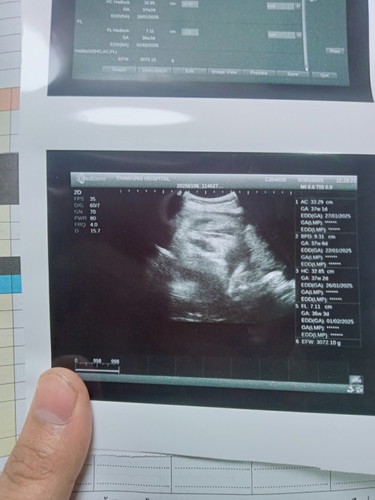

เลยไปตรวจที่ โรงบาลเพื่อให้ชัวร์ผลคือท้องหมอได้7สัปดาห์3วันนับจากประจำถ้านับมาจนถึงปัจจุบันตอนนี้จะอยุ่10สัปดาห์6วันเดือนมารอบสุดท้ายแต่อตอนนั้นที่ไปตรวจโรงบาลหมอทำการคล้ำดูท้องหมอบอกยังไม่มีถุงการตั้งครรค์เลยไม่ได้ซาวด์ดูถึงซาวด์ไปก็ไม่เจอเรยนัดวันที่8ก.คมาเพื่ออัลตราซาวด์ดูน้อง แต่เราดันปวดท้องมีมูกออกเป็นเลือดมื่อวันที่30ที่ผ่านเพราะติดเชื่อปัสวะหมอทำการซาวด์ได้8สัปดาห์2วันหัวใจเต้นปกติ #ปลหมอบอกแค่หัวใจเด็ดเต้นปกติไม่ได้บอกว่ากี่สัปดาห์แต่แม่หฝดูจากผลเองคะ อยากรู้ทำไมถึงผลซาวด์กับจากคำนวนของหมอที่คำนวนจากประจำเดือนไม่ตรงคะใครพอทราบช่วยอธิบายทีคะ ขอบคุณสำหรับคำตอบล่วงหน้าคะ